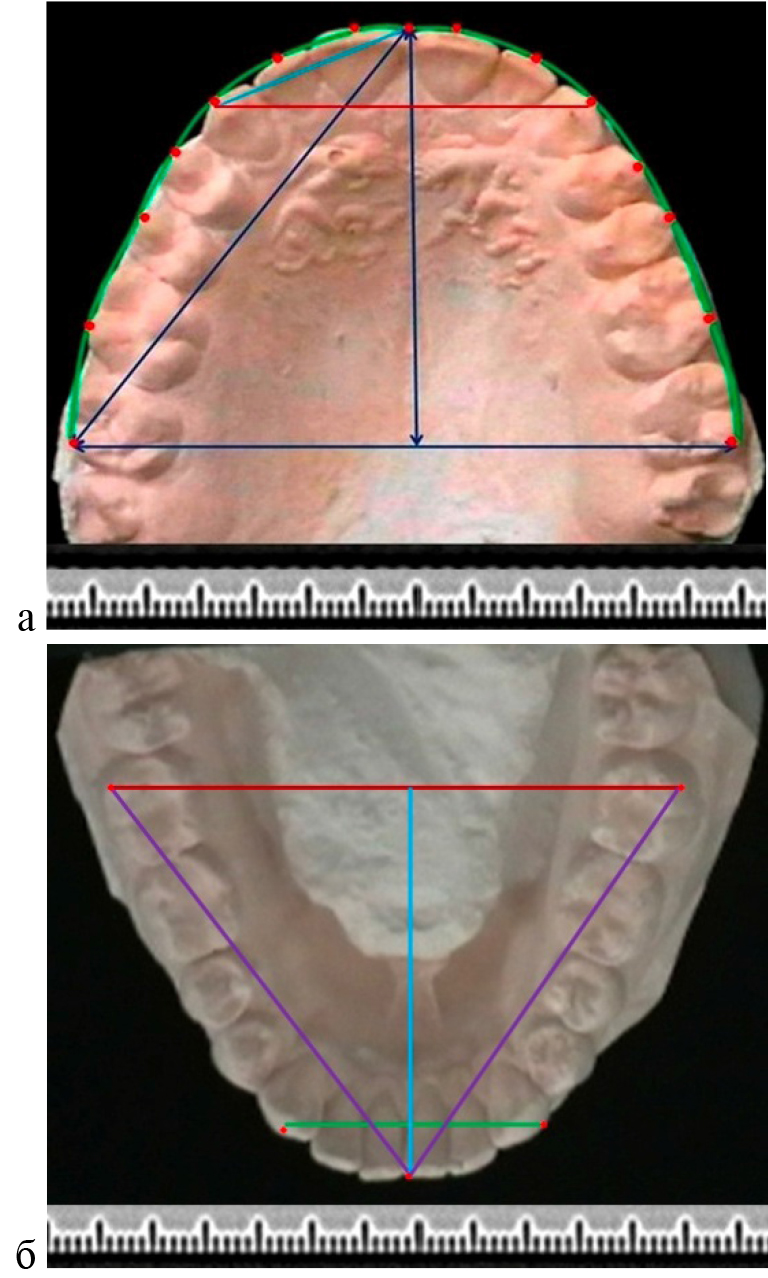

Метод фотостатической биометрии гипсовых моделей челюстей основан на фотографировании моделей с линейкой для удобства последующего масштабирования. На фотографии наносили ориентиры и реперные линии в различных направлениях. Точки для измерения определят исследователь самостоятельно с учетом намеченных задач (рис. 1).

Рис. 1. Фотографии гипсовых моделей верхней (а) и нижней (б) челюсти с нанесенными ориентирами для биометрии и построения геометрических фигур

В соответствии с задачами настоящего исследования на фотографии основным ориентиром была постериальная трансверсаль (ширина между вторыми молярами), которая считается относительно стабильным ориентиром в биометрии зубных дуг. Точка, расположенная на середине указанной линии, позволяла построить условную срединную сагитталь (перпендикуляр) которая при физиологической форме арки проходила между центральными резцами. Диагональные размеры дуги и переднего сектора измеряли от резцовой точки до молярного и клыкового ориентиров.

Углы ротации зубов определяли по отношению к трансверсальной линии зубной арки. При этом условная вестибулярно-лингвальная линия коронки зуба соединяла срединные точки вестибулярного и лингвального окклюзионного контура.